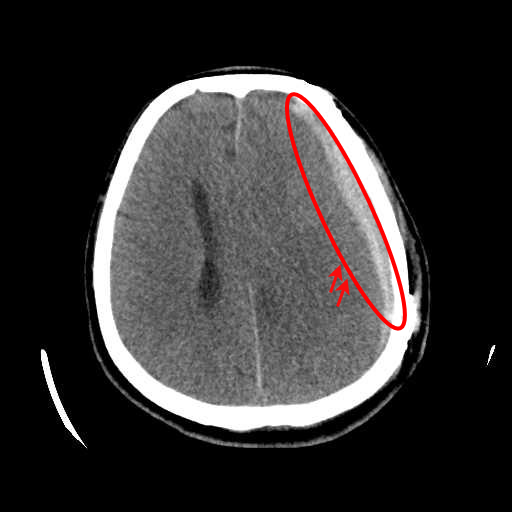

(a) Brain CT scan showing ASDH

Figure 3: (a) Brain CT scan showing ASDH, characterized by recent bleeding with high-density regions, (b) Brain CT scan showing CSDH, indicating older, low-density blood accumulation.